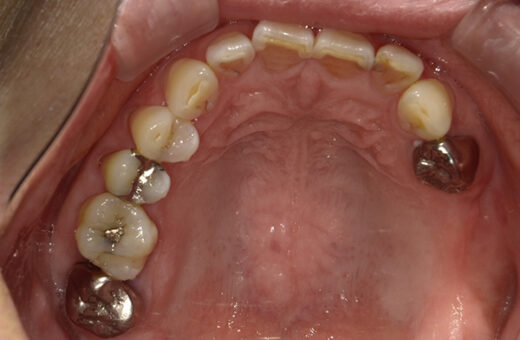

インプラント治療 60代(女性)

治療前

主訴

左上のブリッジが動いていて痛いので咬めない

症例詳細